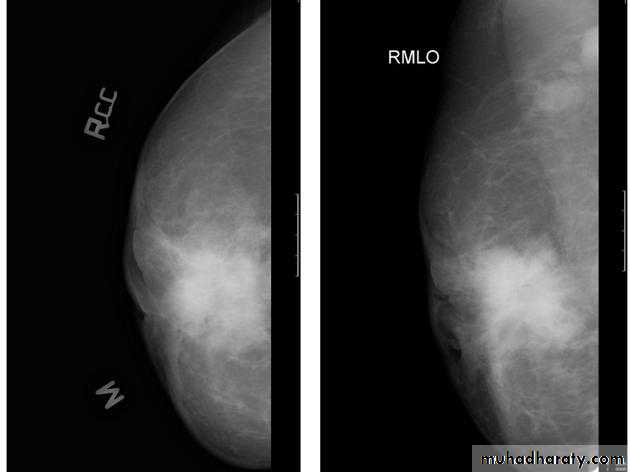

Mammogram deal with the breast mass

Women with a breast lump need to have a mammogram of both breasts. A mammogram is estimated to be able to detect about 90% of breast cancers. This means that about 10% of breast cancers are missed by mammography. Therefore, if a woman or her physician feels a lump and the mammogram is normal, further studies or biopsies are carried out to rule out cancer. Sometimes, a certain pattern of calcium deposits appears on the mammogram that makes the doctor suspicious of cancer. In these cases, it is often recommended that a biopsy be taken that is guided by mammogram images to be sure the correct area is sampledBreast cancer

After all description who can U asses the mass lesion ????

A mass it is calcification & margin

>>>>>> A mass will detected>>>>>> if it is with or without calcifications, change seen on a mammogram.

>>>>>> it is Margin

Masses are areas that look abnormal in mammogram that can be many things, not only CA including cysts (non-cancerous, fluid-filled sacs) and non-cancerous solid tumors (such as fibro adenomas), but must aware they sometimes may be a sign of cancer